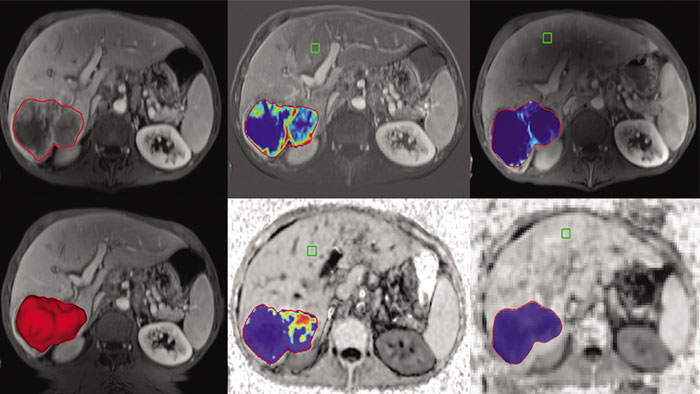

Semi-automatic tumor quantification

This semi-automated 3D (Volumetric) tumor response assessment tool, based on EASL (European Association for the Study of the Liver) criteria incorporates functional information from contrast-enhanced scans.